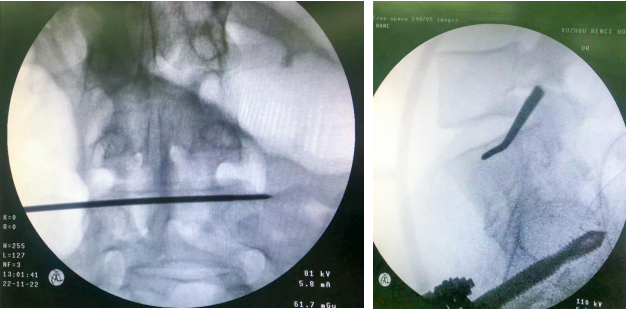

根据患者的伤情,创伤骨科任海东主任组织医生讨论手术方案,最终决定采用“机器人导航下多发性骨盆骨折复位内固定术”。骨盆骨折微创复位技术的优点是创伤小、费用低、恢复快、并发症少、固定可靠,能为病人快速康复奠定基础。

经充分术前准备并与患者沟通,任海东、信远、吴学业手术团队对患者实施了微创手术,仅通过几个1-3公分的小切口就完成了手术,出血量约50ml。